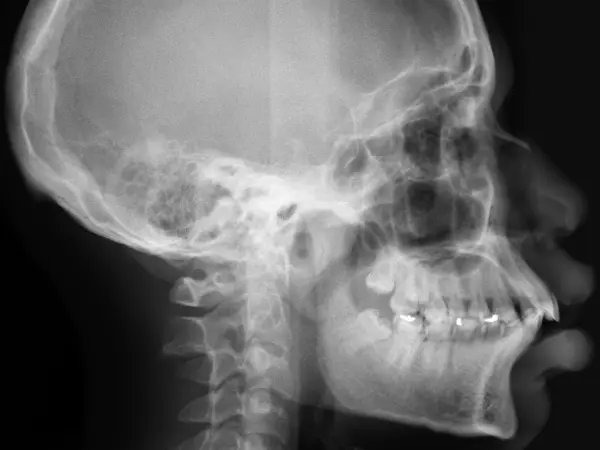

An open bite occurs when the top and bottom rows of teeth don't touch when the mouth is closed. Open bites can occur in the front of the mouth (anterior open bite) or the back (posterior open bite), although front-teeth open bite is more common. Genetics or prolonged thumb-sucking in childhood are common culprits of open bites.

An overbite is a too-large overlap between the top teeth and the bottom teeth. The top teeth hang too far over the bottom teeth: in severe overbites, the bottom teeth may even make contact with the roof of the mouth, causing damage to the tissue and bone. While a small overbite is normal in a proper bite, too large overbites are considered malocclusions and should be treated with orthodontic care.

Crossbite, or underbite, is a malocclusion when the top and bottom rows of teeth overlap improperly. The bottom teeth are set past the top teeth when the jaw is closed. This can occur in the front or back teeth, and can create a combination of overbite and underbite, or underbite and open bite.

An overjet is a condition where there's a large horizontal gap between the top and bottom teeth when the mouth is closed. This gap makes the front teeth stick out. This condition is often called "buck teeth." A small overjet is normal, but a larger one requires orthodontic treatment.